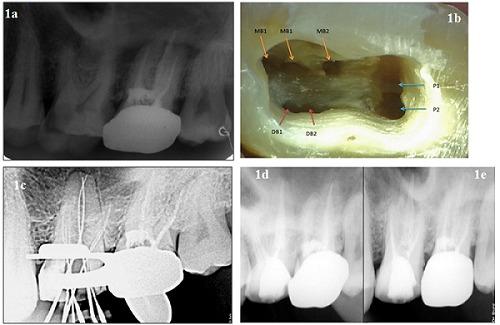

The main objective of this case report is to present a rare root canal configuration of maxillary molar with seven root canals; three mesiobuccal, two palatal and two distobuccal canals diagnosed during treatment procedure confirmed by spiral computed tomography. A thorough knowledge of root canal morphology, proper clinical and radiographic examination, and use of dental operating microscopes are necessary for successful clinical outcomes. This article highlights the variations in the morphology of maxillary first molar and use of the latest techniques in successful diagnosis and negotiation of the additional canals.

本病例报告的主要目的是呈现一例罕见的上颌磨牙根管形态,该牙有七条根管;在治疗过程中诊断出三条近中颊根管、两条腭根管和两条远中颊根管,螺旋计算机断层扫描证实了这一情况。要获得成功的临床治疗效果,全面了解根管形态、进行适当的临床和影像学检查以及使用牙科手术显微镜是必要的。本文重点介绍了上颌第一磨牙形态的变异情况以及在成功诊断和疏通额外根管中使用的最新技术。